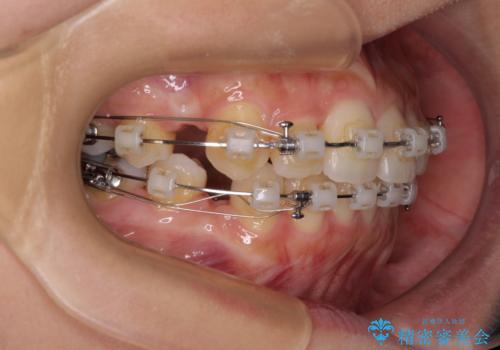

- 矯正装置

- クリアブラケット

上下左右の第一小臼歯4本を抜歯して治療を行うことがセオリーでしたが、左下は第二小臼歯が銀歯であったため、イレギュラーではありますが、そちらを抜歯しました。

その影響で治療期間は長くなりましたが、処置していない歯を保存することができました。